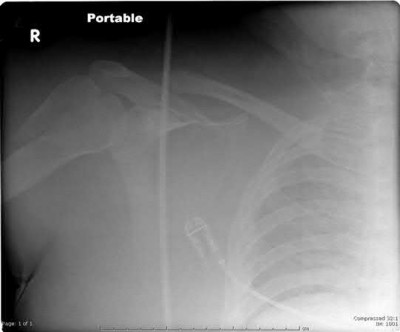

A 44-year-old male is struck by a vehicle while riding his bike. In the trauma bay, he complains of right shoulder pain . Upper extremity physical exam reveals no neurologic deficits, and an initial radiograph of the shoulder is shown in Figure A. A CT scan of the shoulder shows 1cm of posterior displacement of the tuberosity fragment. Which of the following is true regarding this injury?

The radiograph in Figure A demonstrates a posteriorly displaced greater tuberosity fracture. These injuries are often associated with anterior shoulder dislocations, and concomitant rotator cuff tears. The subscapularis attaches to the lesser tuberosity, and is not a deforming force. Open reduction and internal fixation (ORIF) is usually the treatment of choice, and it is well accepted that more than 5mm of displacement is an indication for surgery in patients that require overhead function of the arm.

Flatow et al evaluated 12 patients who were an average of five years status post ORIF of displaced greater tuberosity fractures. All fractures healed without postoperative displacement. Six patients had an excellent result and six had a good result.

Platzer et al retrospectively analyzed functional and radiographic results of 52 patients with operative treatment of displaced greater tuberosity fractures at an average time of 5.5 years from surgery compared to 9 patients with equivalent injuries treated non-operatively. Evaluation of the results of the surgical study group and the nonoperative control group, patients with reduction and fixat ion of greater tuberosity fractures had significantly better

results on shoulder function than did those with conservative treatment.